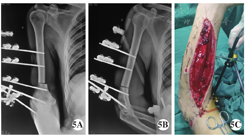

手术方法 急诊入院后完善相关术前检查,在臂丛阻滞麻醉下行右臂清创,彻底剪除污染坏死组织后见:右臂中下段宽约5.0 cm软组织环形缺损,肱二头肌长头、肱二头肌短头、肱肌、肱桡肌部分起点、肱三头肌外侧头及大部分肱三头肌长头、肱三头肌内侧头、肱三头肌腱节段性缺损,肱动脉及伴行静脉、桡神经、正中神经节段性缺损约4.0 cm,软组织仅有部分肱三头肌长头、内侧头肌肉及尺神经相连,约占肢体横截面的1/10,尺神经连续性完整,外膜有长约3.0 cm明显挫伤,肱骨干连续性完整,骨膜缺失约3.0 cm(图3)。使用9 000 ml生理盐水冲洗创面,更换器械手套,重新铺单。微型摆锯截除外露肱骨干约4.3 cm(图4),肱骨远、近两端经皮各置入2枚直径为5.0 mm外固定支架半针,截骨端对合复位后,碳素杆外固定支架固定。显微镜下直接吻合肱动脉及伴行静脉重建肢体血运,正中神经、桡神经断端缝接前分别剪除少许,外露正常神经乳突,无张力下显微缝接,松解尺神经外膜,肌肉断端采用"8"字缝合,缝合时尽量带着肌腱膜缝合,使肌肉缝合断端结实紧密,并吻合贵要静脉及头静脉,皮肤创缘用3-0丝线直接缝合,前臂筋膜室减张后覆盖VSD敷料,桡骨中段拧入1枚直径4.0 mm外固定支架半针,连接臂外架固定肘关节于屈肘30°位。术后1周再植肢体血运良好,前臂肿胀明显减轻,减张切口直接缝合(图5)。术后4周,拆除跨肘关节外固定支架,行上肢关节被动功能锻炼。

A.正位片 A. Anteroposterior view; B.侧位片 B. Lateral view; C.右前臂外观 C. Appearance of right arm